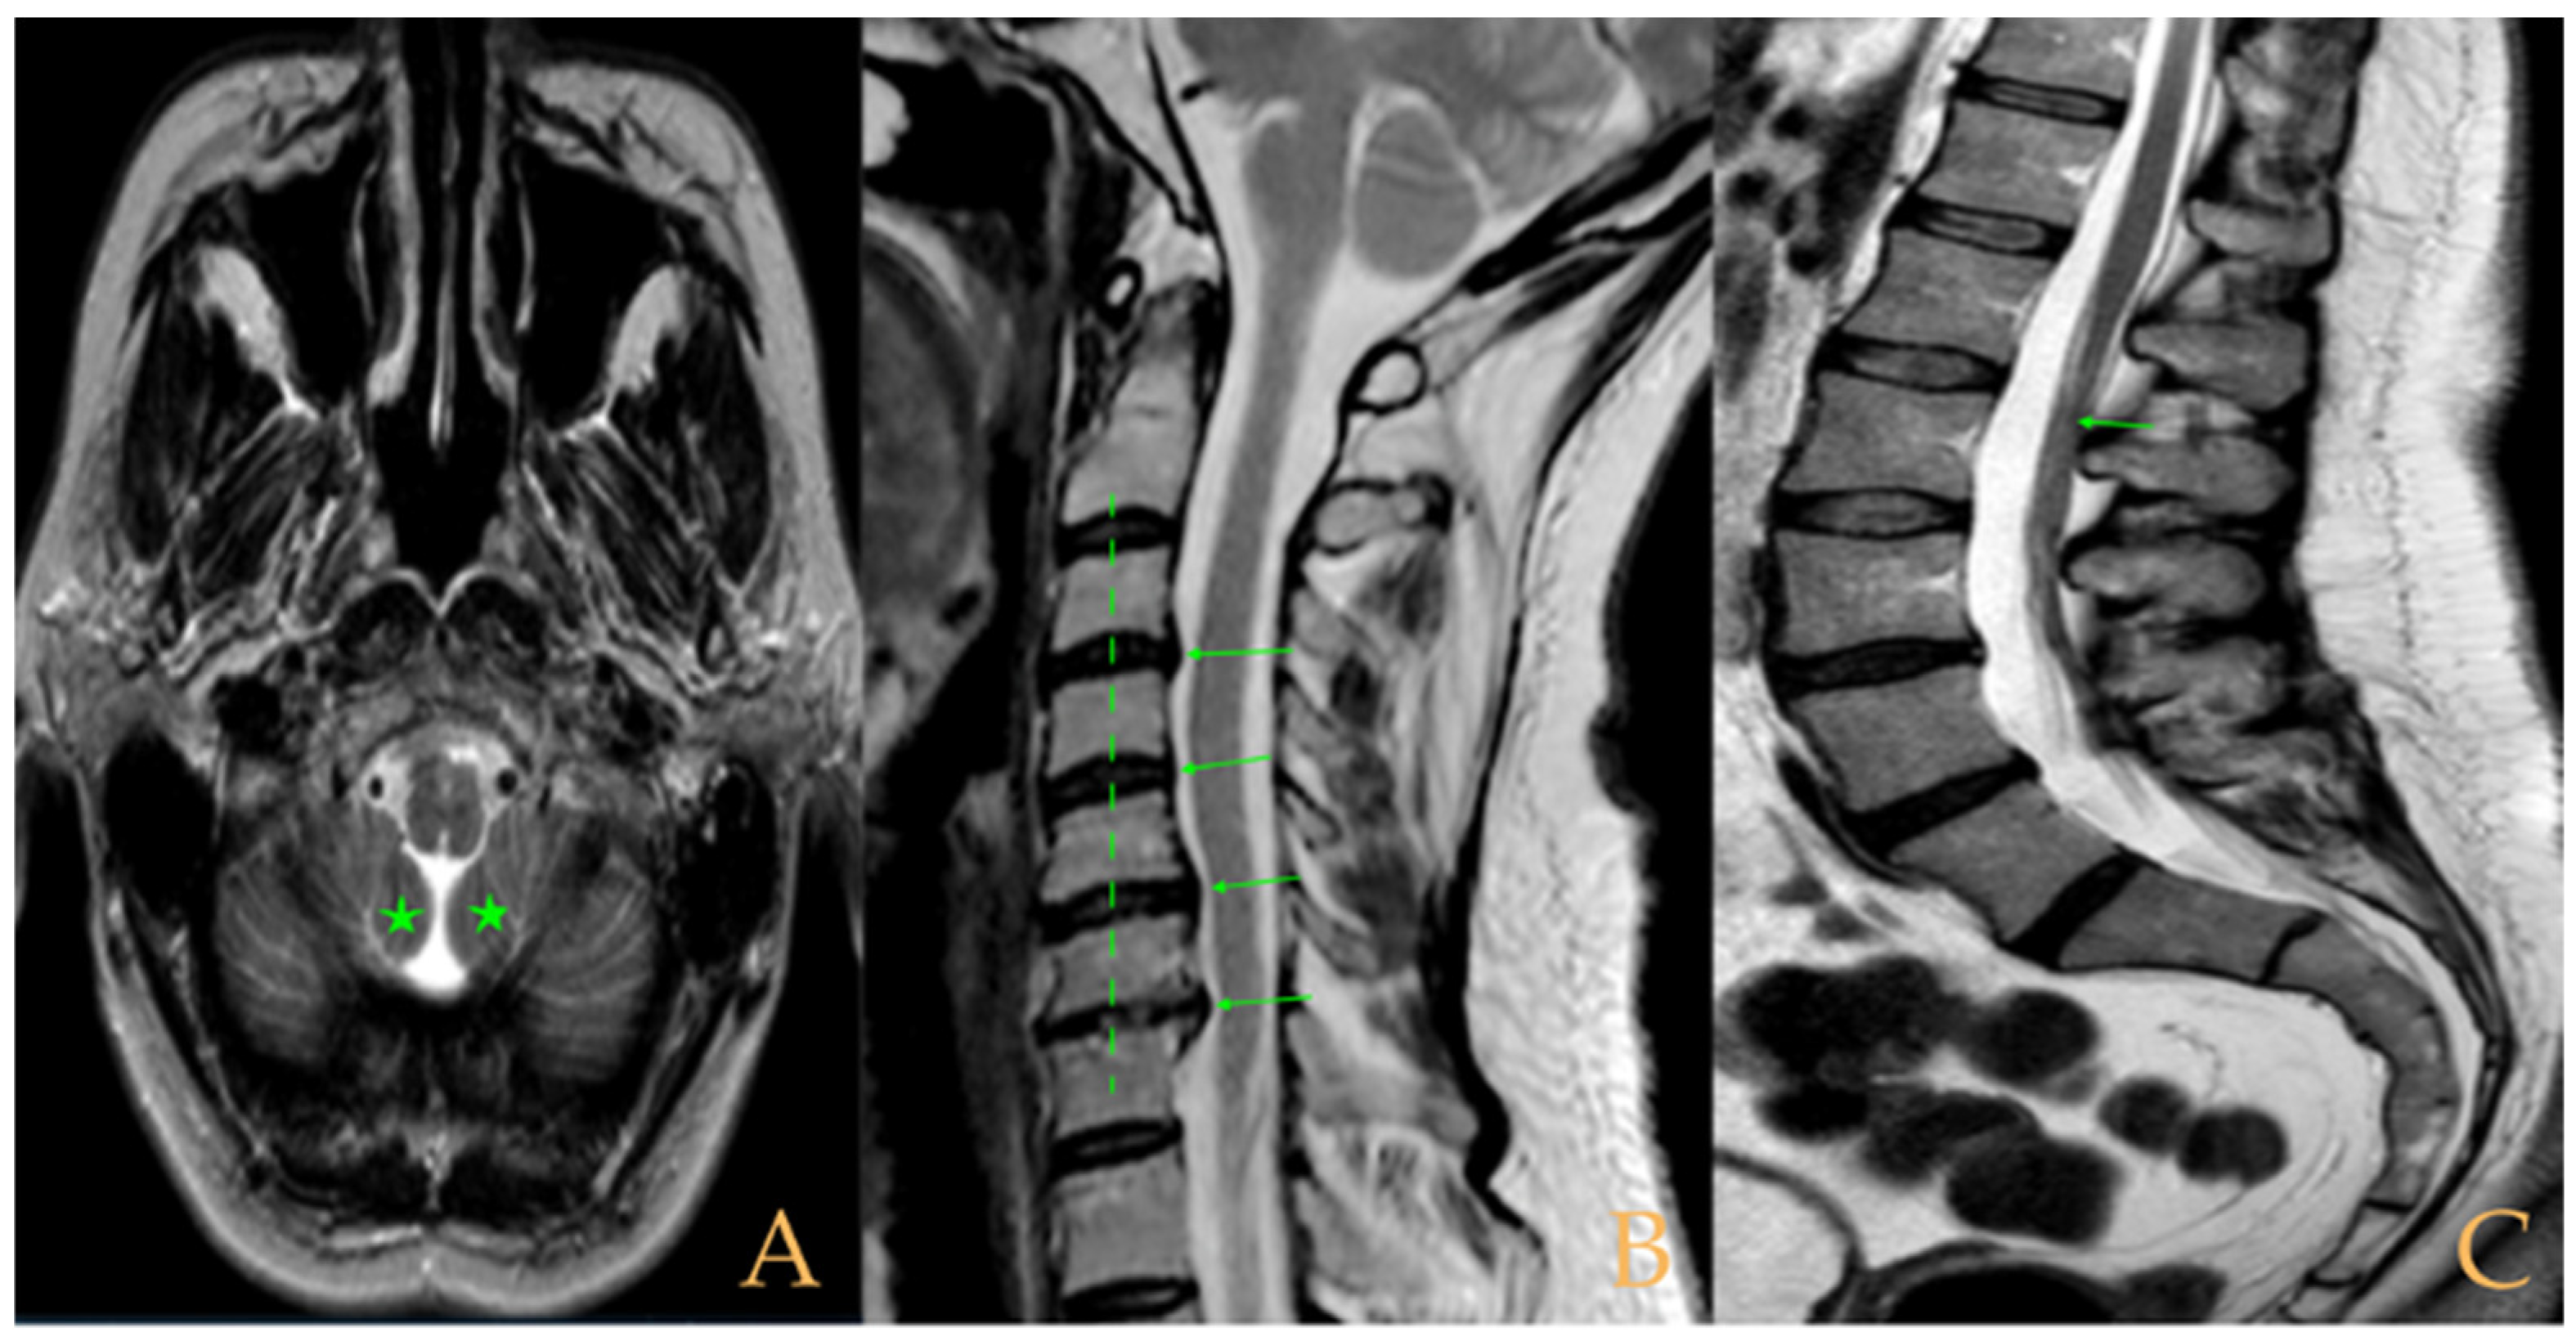

The MRI showed descent of the cerebellar tonsils, increased supracerebral space, and postsurgical repercussions of the sphenoid sinus in the right half. Empty sella turcica. Micro lacunae bilaterally in hemispheres, basal ganglia, and white matter. Straightening of the cervical spine. Cervical spinal cord with tense aspect and inferior lateral displacement, the thoracic portion appears tense with slight ischemia and oedema. Protrusions: C3-C4, C5-C6-C7, T7-T8, and L3-S1. Lumbar hyperlordosis. Sacrococcygeal hyperkyphosis. Ischemia and oedema in epiconus. Low conus medullaris at the level of the upper third of L2 vertebral body. Tarlov cyst at S2 (left) (Figure 4). Proximal filum terminale externum visible. Levoconvex lumbar scoliosis on the spine X-ray estimated at 6°; dextroconvex cervical and thoracic scoliosis estimated at 4°.

Figure 4.

Imaging of patient 4. A: Cranial MRI with visible descent of the cerebellar tonsils in the foramen magnum (stars); B: cervical MRI with straightening of the cervical spine (interrupted line) and cervical multiple disc disease (arrows); and C: lumbar MRI with conus medullaris at the upper third of L2 (arrow).